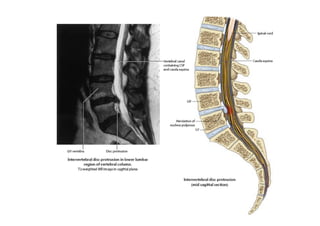

Disc protrusion-T2 weighted magnetic resonance images

of the lumbar region of the vertebral column. A. Sagittal plane. B. Axial plane.